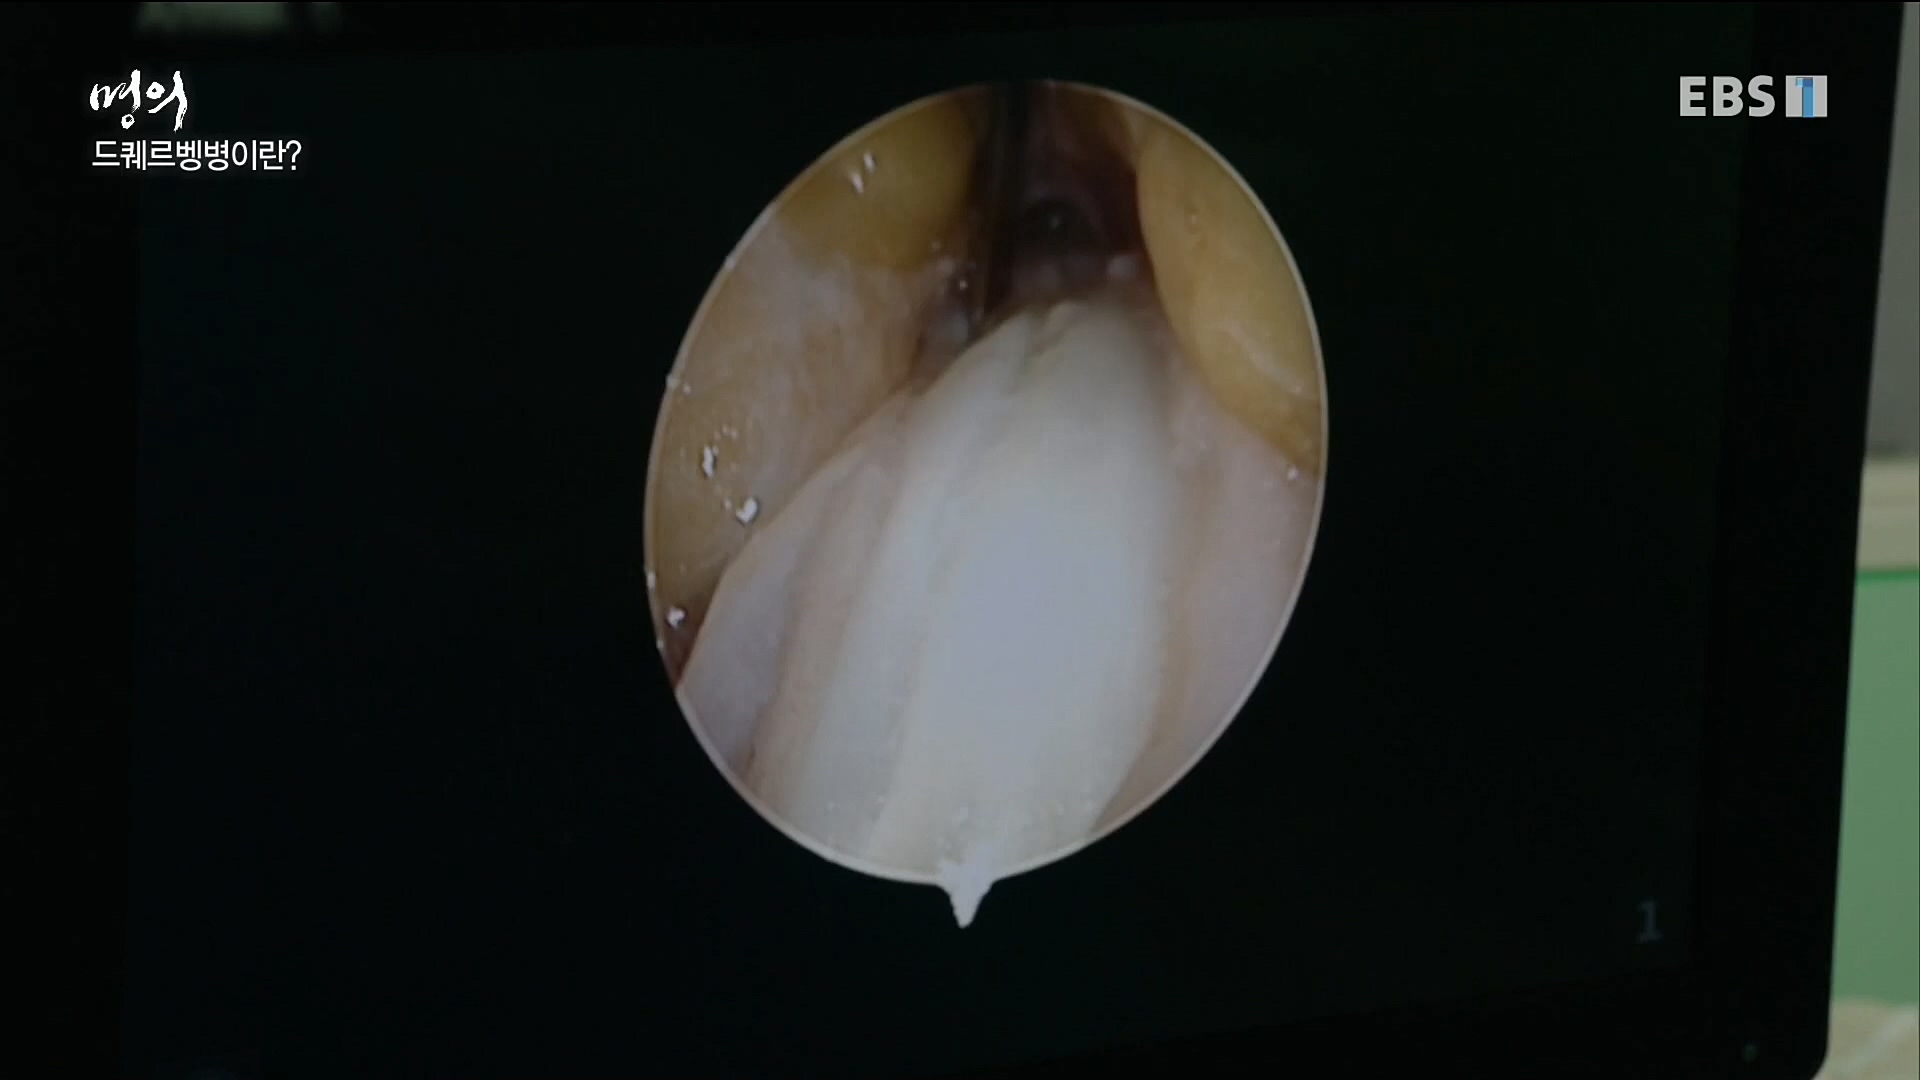

작은 양손에 모여 있는 뼈의 개수는 무려 신체의 1/4을 차지한다. 작은 손안에 수많은 뼈와 여러 신경이 모여 있는 것이다. 드퀘르벵병, 손목터널증후군,...

명의' 최윤락 교수와 함께 손목터널증후군, 드퀘르벵병, 팔꿈치터널증후군, 흉곽출구증후군, 손목 물혹(결절종), 방아쇠수지 등 손과 팔에 생길 수...

이날 EBS 명의 '손이 보내는 경고, 저림과 통증' 편에서는 정형외과 전문의이자 수부외과 세부전문의 최윤락 교수와 함께 손과 팔에 생길 수 있는...